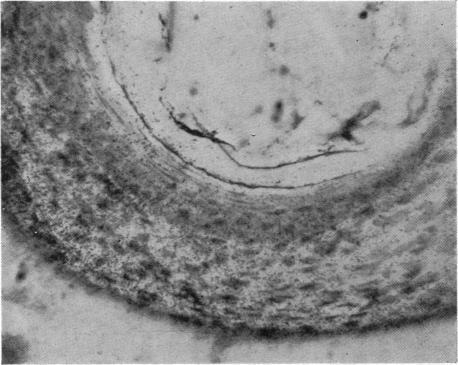

The dormant cancer cell.